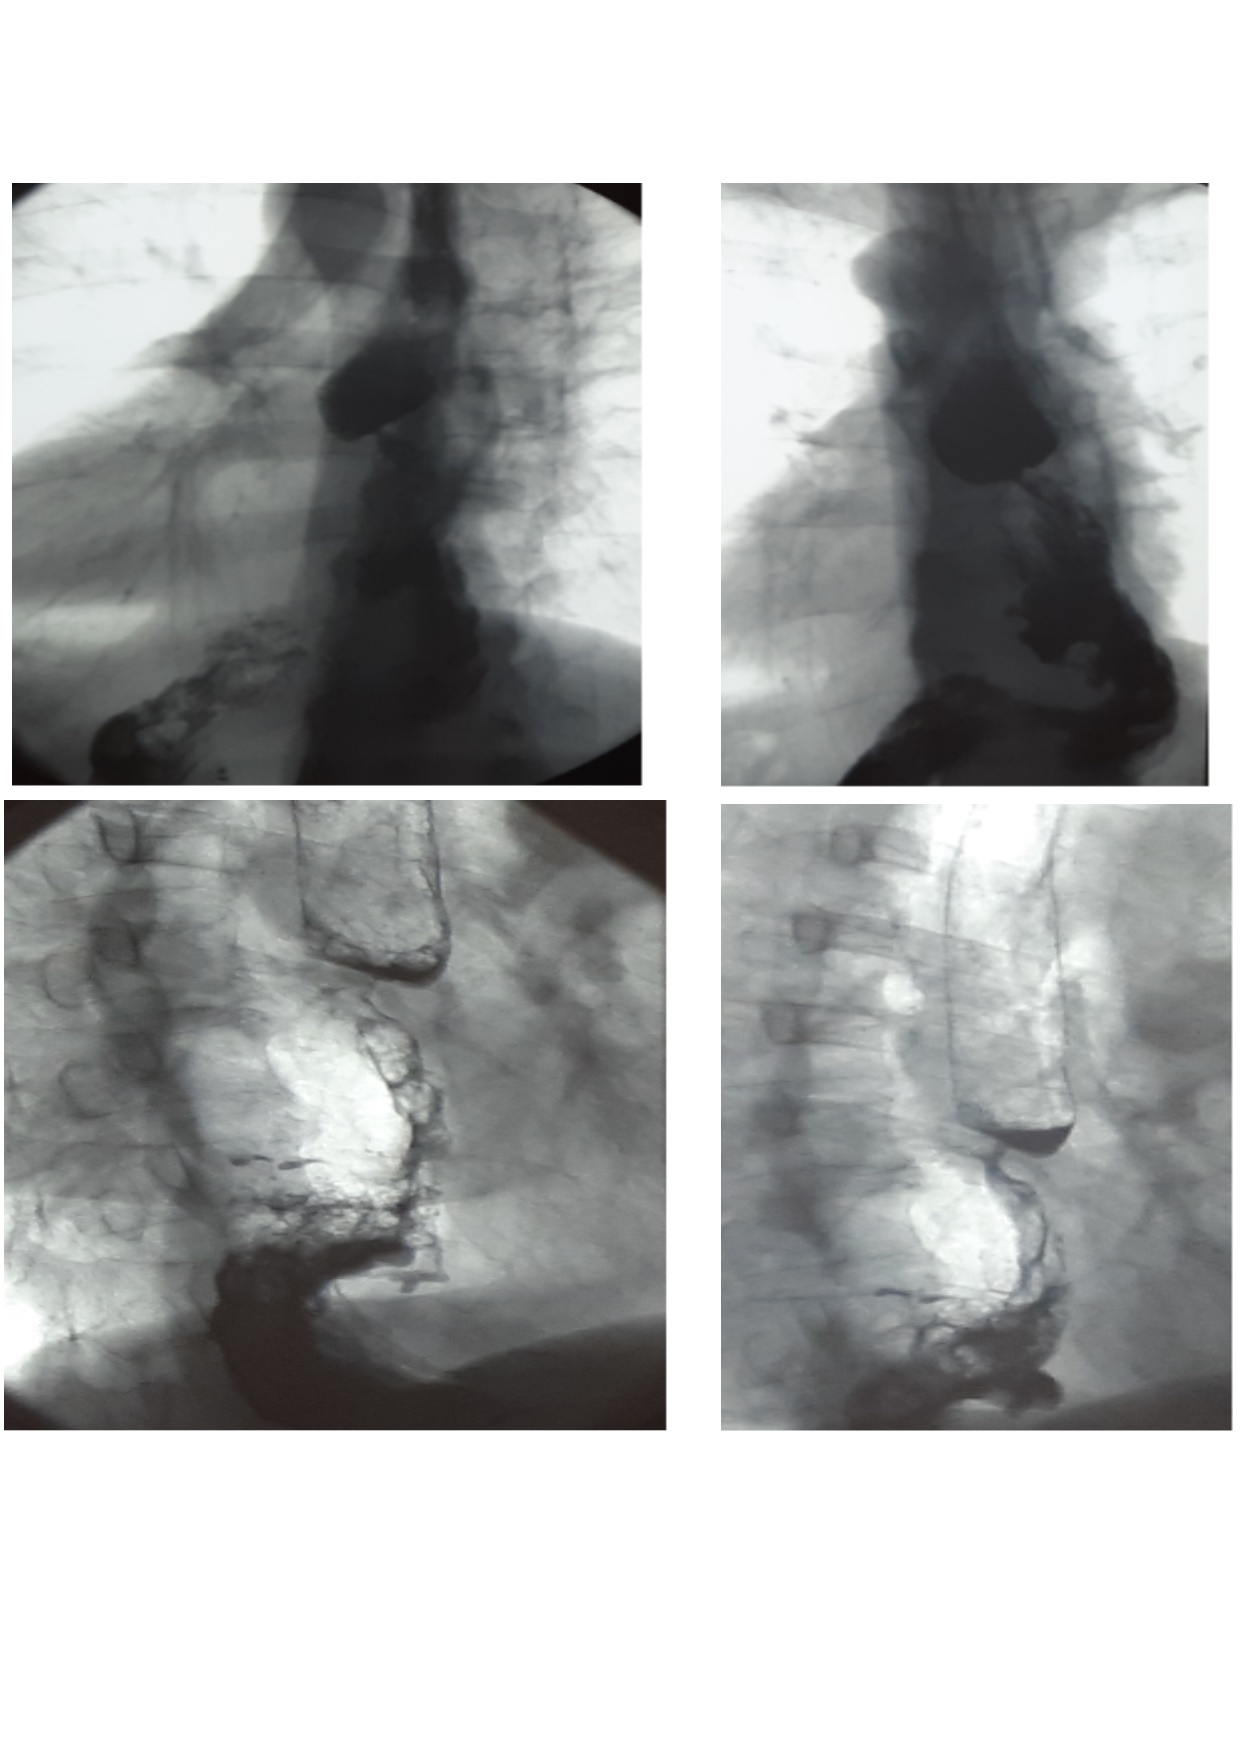

Contrast multiposition examination of the esophagus, stomach, duodenum after peroral intake of barium sulfate suspension (X-ray examination and X-ray photography in the frontal, lateral and oblique projections) revealed signs of cardioesophageal cancer (Figure 1).

Fig. 1. Radiographic contrast study of the esophagus and stomach: In the abdominal part of the esophagus and in the cardial part of the stomach a defect of filling is determined 4 x 3 cm with irregular edges, mucosal folds in the zone are not observed. Against the background gas bubble of the stomach the shadow of the tumorous formation is visualized. The fasting stomach contains insignificant amount of fluid and mucus. Emptying of the contrast substance from the stomach is not disturbed. The bulb and other parts of the duodenum are without changes

Endoscopic and X-ray examinations (Figure 3) revealed cicatrical stenosis in the zone of gastroanastomose. After per os intake of barium suspension, narrowing of the lumen to 0.4 cm along 0.7 cm length was determined in the region of anastomose in a series of X-ray pictures. Evacuation through the esophagus, transplant, a part of stomach in the abdominal cavity and duodenum was visible.

Fig. 3. Radiographic contrast examination of the esophagus and stomach in 4 months after surgery